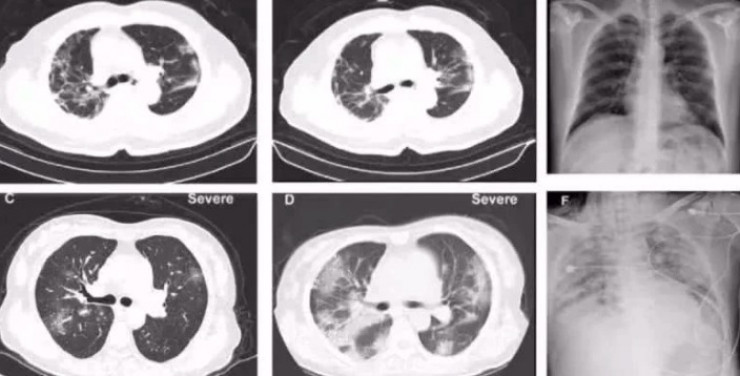

Во время госпитализации у больного не наблюдались повышенная температура, кашель и другие симптомы. На 10-й день после поступления в больницу у него появились дискомфорт в горле в виде зуда и высокая температура, компьютерная томография показала наличие инфекционных очагов на обоих легких.

На 20-й день госпитализации повторная томография легких показала дальнейшее распространение очагов инфекции в обоих легких, на 28-й день больной скончался, причиной смерти была установлена "пневмония, вызываемая новым типом коронавируса, дыхательная недостаточность".

Компьютерная томография легких пациента с коронавирусной инфекцией. © Tencent News

"Мы не знаем, где находится "враг", какое "оружие" он использует для атаки и какими методами мы можем эффективно обуздать его силу. Патологоанатомическая работа похожа на "разведку". Благодаря патологической анатомии и последующим исследованиям распространение вируса в организме человека можно наблюдать под микроскопом. Можно будет понять, какие органы, ткани и клетки пострадали больше всего, в чем слабость "врага". Компьютерная томография показала появление симптомов "матового стекла" в легких пациентов", - рассказал доктор Лю Лян.